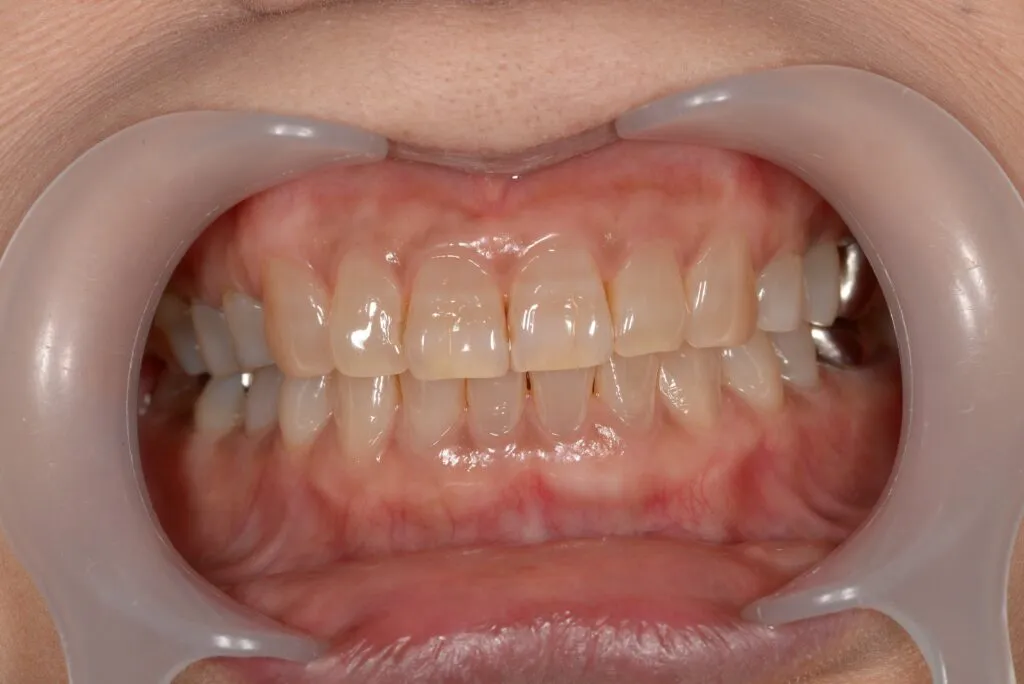

case2

Before

After

治療内容 | 口腔内診査〜カウンセリング 歯周初期治療 仮歯を入れ機能的な評価 最終的な型取り〜装着 |

治療期間 | 1ヶ月〜2ヶ月 |

治療回数 | 5回 |

リスク | クリーニングにこない場合噛み合わせの確認ができないため装着していった人工物が割れてしまう可能性があるため、今後のメンテナンスが必須となる |

費用(税込) | 約¥143,000 |